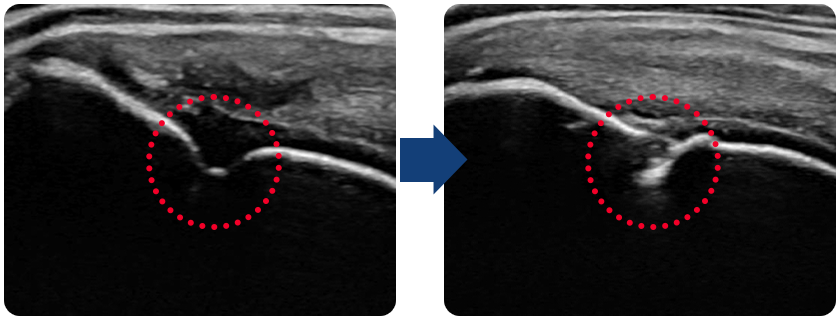

4세대 인대주사성분으로

재생된 회전근개

(진단명: 회전근개 부분파열)